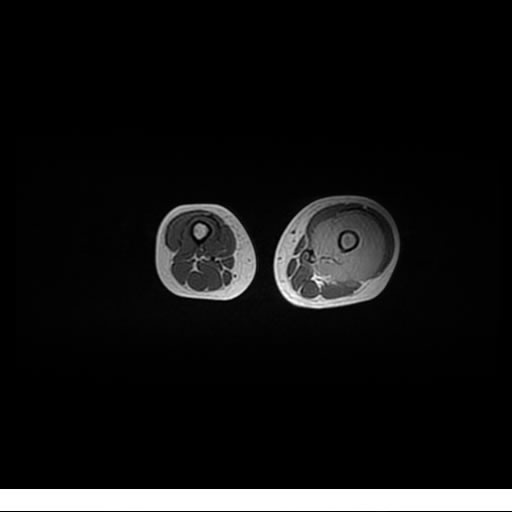

Se realiza estudio de MRI de muslo izquierdo en diferentes planos, con secuencias de Spin Echo, GRE; ponderadas a T1 y a T2, se utilizan pulsos de saturación de grasa y se administra medio de contraste IV a base de Gadolinio en base al peso del paciente.

La diáfisis femoral izquierda muestra reacción perióstica importante, se extiende desde el cuello del fémur, invade trocánteres, diáfisis femoral, medial y distal, es compatible con un proceso infeccioso óseo, el complejo muscular del muslo se ve edematizado.

Hallazgos en Resonancia Magnética (RM)

La resonancia es la modalidad de elección para valorar la extensión intramedular y la infiltración en tejidos blandos, brindando una imagen más detallada del compromiso tumoral. Los hallazgos característicos incluyen:

Lesión de señal heterogénea en secuencias T1 (hipointensa) y T2/STIR (hiperintensa), que refleja necrosis, hemorragia y contenido celular diverso.

Realce intenso y heterogéneo tras la administración de contraste (gadolino), lo que indica vascularización tumoral.

Compromiso de la médula ósea adyacente y de estructuras vecinas, como músculos y neurovasculatura.

Posible presencia de edema óseo y necrosis central.